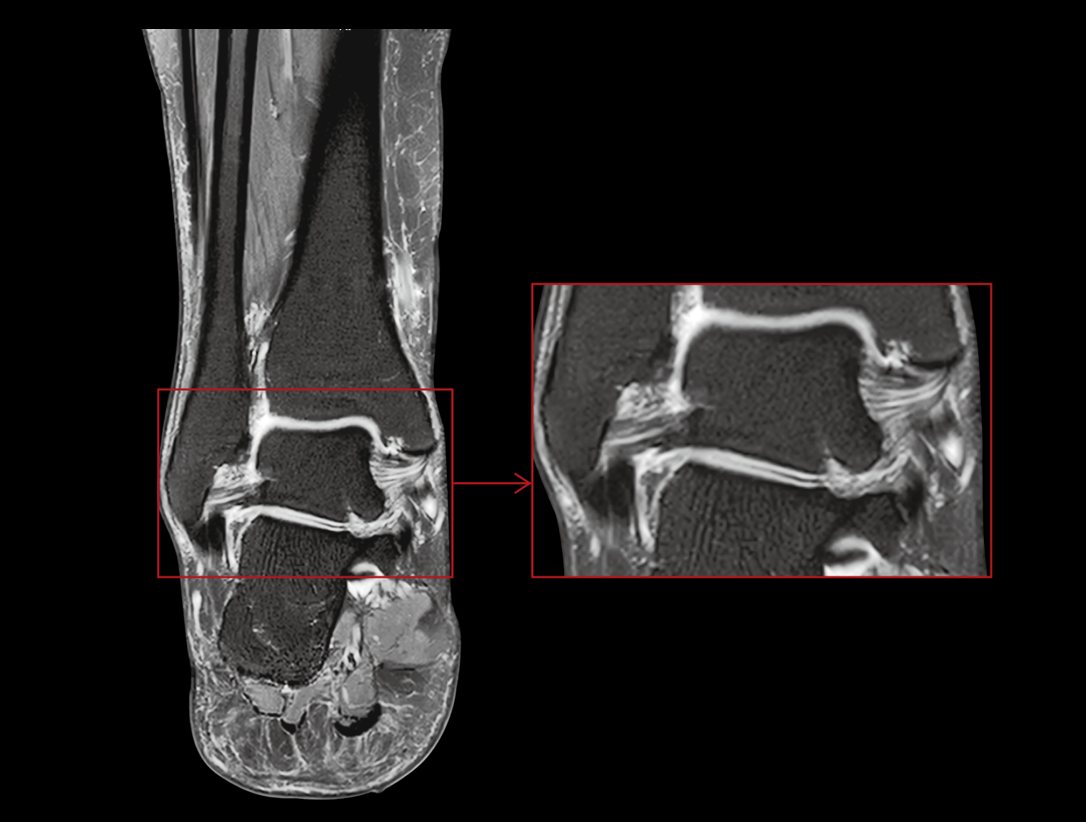

Wysokie parametry gradientu poprawiają szybkość pozyskiwania danych i skanowania, co pozwala zwiększyć wydajność pracy.